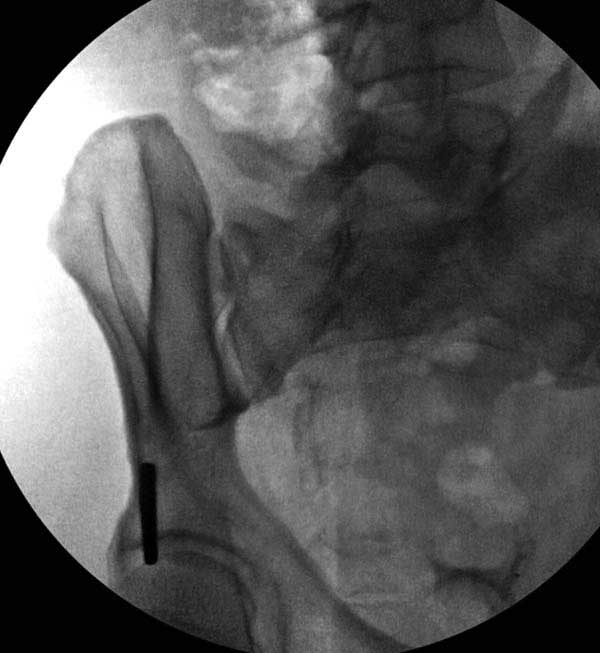

Представлены снимки техники проведения стержней. Через место прикрепления прямой мышцы в Inferior Iliac Spine в направления вырезки создается жесткость. Weber clamp изнутри таза для репозиции, и фиксация после репозиции перелома крыла подвздошной кости. Наружный аппарат удален, нагрузка предполагается через два месяца.